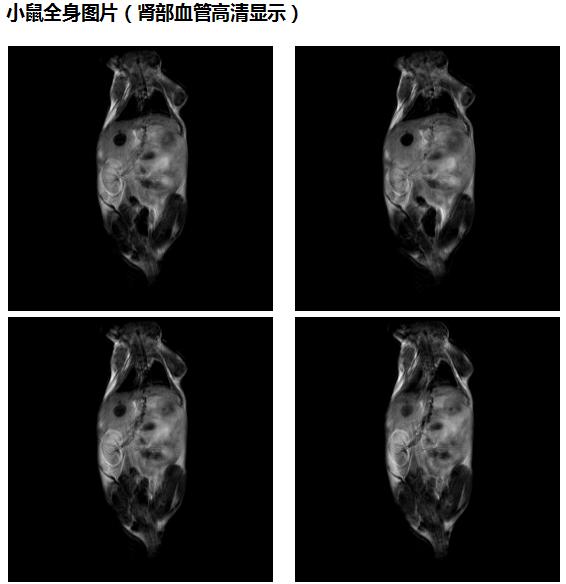

4、核磁共振成像科研性实验样品观察(小鼠,小动植物体等样品的三维、二维成像实验),小鼠分子影像科研实验研究;

肿瘤鼠图片